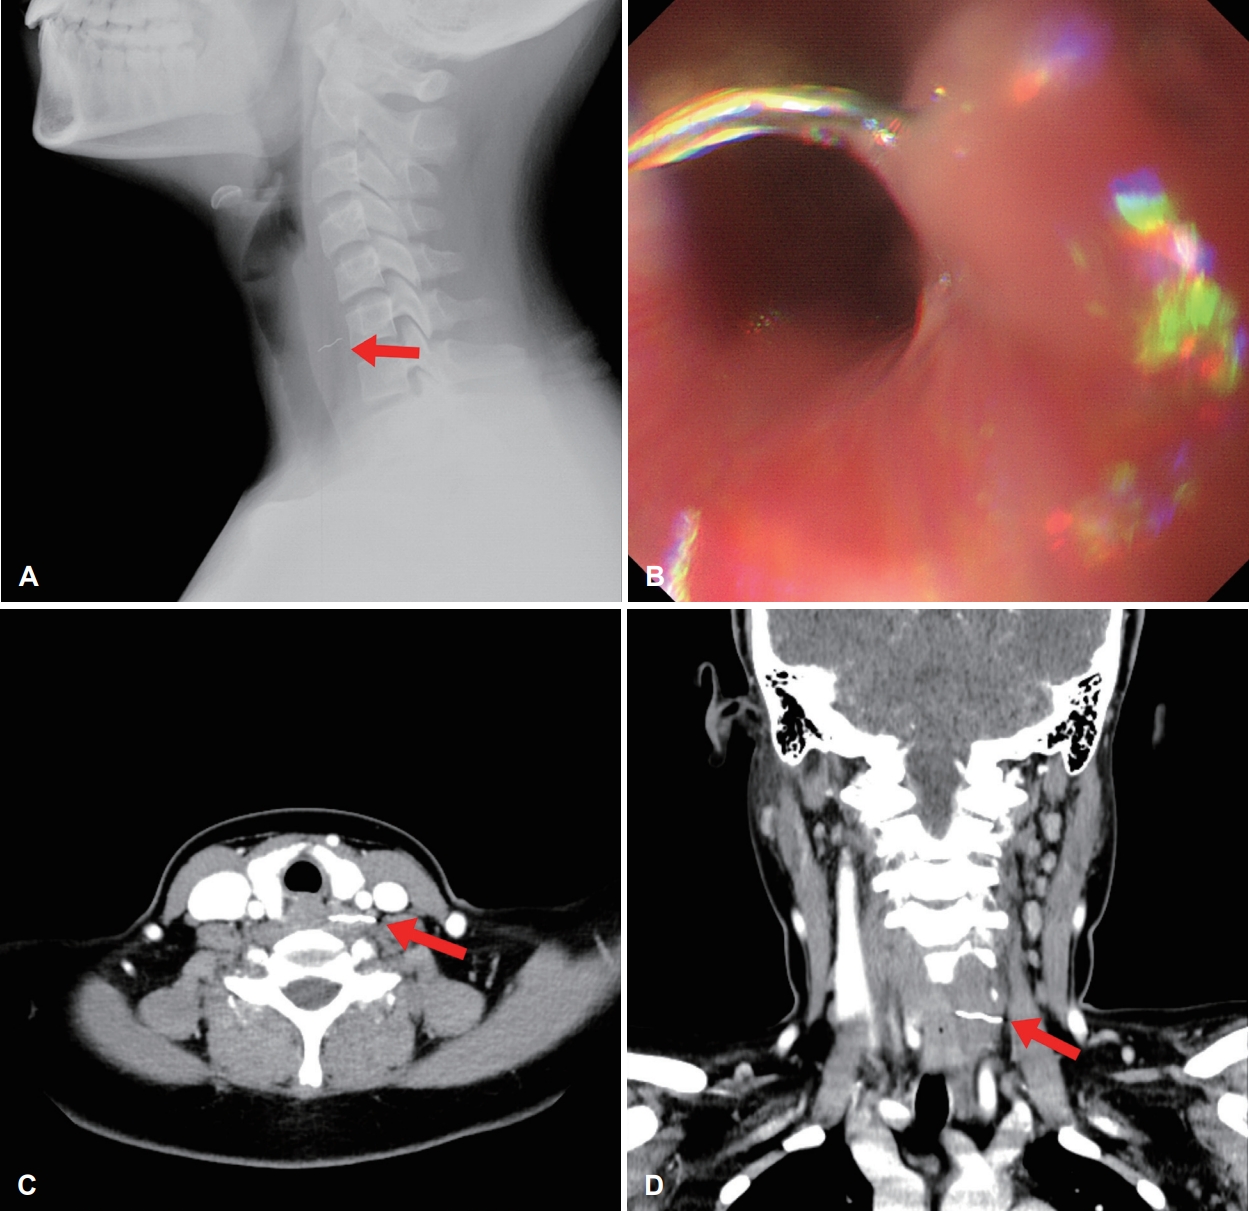

13세 여아가 본원 응급실로 내원하였다. 내원 1일 전 식사 후 목의 이물감 및 통증이 지속되어 타 병원 방문하여 시행한 경부 측면 단순 방사선 영상에서 2 cm 가량의 이물 의심 소견이 확인되었다(Fig. 1A). 과거력에서 특이 소견 없었으며, 내원 후 생체 징후는 혈압 100/60, 맥박 86회, 호흡 20회, 체온 36.6도였다.

경부 측면 단순 방사선에서 확인된 이물의 위치는 경추 6번 전방에 위치한 양상이었으며, 본원 응급실에 내원한 당일 소아과에서 소화기 위 식도내시경으로 식도 내의 이물을 확인하였다. 당시 금속성 물질의 이물은 내시경상에 상부식도괄 약근의 직하방, 식도 내측면에서 이물이 확인되었으나, 이물 끝 부분이 식도 벽에서 경부 공간으로 돌출되어 고정되어 있는 양상이었다(Fig. 1B). 내시경으로 제거를 시도하였으나, 이물 제거가 되지 않았으며, 이후 시행한 경부 컴퓨터전산화단층촬영(CT)상 경장근(longus colli muscle)에 이물이 위치함을 확인하였다(Fig. 1C and D). 그 외에 후인두 부위의 염증 및 삼출액 소견은 확인되지 않았다.